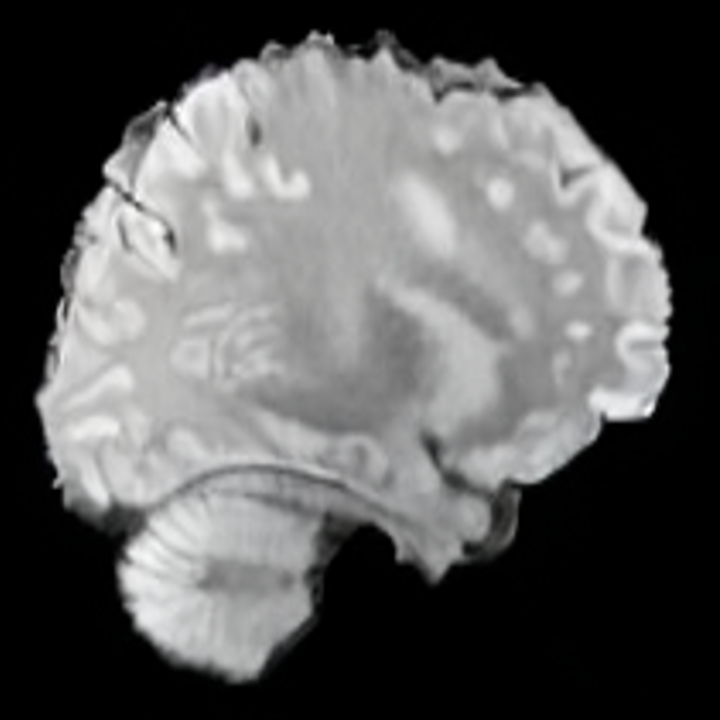

In this work, we present X-Diffusion, a cross-sectional diffusion model tailored for Magnetic Resonance Imaging (MRI) data. X-Diffusion is capable of generating the entire MRI volume from just a single MRI slice or optionally from few multiple slices, setting new benchmarks in the precision of synthesized MRIs from extremely sparse observations. The uniqueness lies in the novel view-conditional training and inference of X-Diffusion on MRI volumes, allowing for generalized MRI learning. Our evaluations span both brain tumour MRIs from the BRATS dataset and full-body MRIs from the UK Biobank dataset. Utilizing the paired pre-registered Dual-energy X-ray Absorptiometry (DXA) and MRI modalities in the UK Biobank dataset, X-Diffusion is able to generate detailed 3D MRI volume from a single full-body DXA. Remarkably, the resultant MRIs not only stand out in precision on unseen examples (surpassing state-of-the-art results by large margins) but also flawlessly retain essential features of the original MRI, including tumour profiles, spine curvature, brain volume, and beyond. Furthermore, the trained X-Diffusion model on the MRI datasets attains a generalization capacity out-of-domain (e.g. generating knee MRIs even though it is trained on brains). The code is available on the project website https://emmanuelleb985.github.io/XDiffusion/.

Contributions: (i) We introduce X-Diffusion, a cross-sectional diffusion model that generates MRI slices conditioned on a single input MRI slice or multiple slices. The proposed X-Diffusion achieves state-of-the-art results on MRI reconstruction and super-resolution compared to recent methods on BRATS, a large public dataset of annotated MRIs for brain tumours. (ii) We adapt our X-Diffusion to leverage paired and registered full-body MRI and DXA images from UK Biobank dataset to generate full-body 3D MRI from a single DXA for the first time in the literature. (iii) We validate the generated MRIs on a wide range of tasks that ensure the generated MRIs retain important features of the original MRIs, including tumor profiles, spine curvature, brain volume, and more, without using this meta-information in the generation process. (iv) We showcase the generalization of trained X-Diffusion on different datasets (knee MRIs) illustrating the potential of X-Diffusion to be the first 3D volumetric foundation model in medical imaging.

5.3 Out-of-Domain Generalisation

One way to test the generalization capability of the trained X-Diffusion is to test it on a completely different domain from an MRI dataset not seen during training. We report the single-slice results on NYU fastMRI [37, 82], a knee MRI dataset, using the X-Diffusion trained on the BRATS brain MRIs. The results are shown in Figure 9 and Table 2. It shows how successfully X-Diffusion is able to generate knee MRIs from a single image, despite not seeing knees at all in training. To qualitatively assess how realistic our generated 3D volumes were (produced from a single slice), we gave 20 generated examples alongside their real MRI counterparts to an expert orthopaedic surgeon. He was then asked to identify the real example from a given pair. The surgeon identified with certainty only 10 real knee MRIs out of 17, while could not decide on the remaining 3 of the 20 MRI pairs. This further validates the generated out-of-domain MRIs.